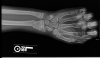

Owwww.Surgury is the answer on this one. Wires need to be added to help re-align the bones.i dont think that will need surgery...but it look painnnnnnnnnnnnnnnful!![]()

Or they might just do what they did to my friend when he broke his wrist.Surgury is the answer on this one. Wires need to be added to help re-align the bones.

Surgury is the answer on this one. Wires need to be added to help re-align the bones.

Or they might just do what they did to my friend when he broke his wrist.

Put some of those pins that stick outta your wrist while the cast is on, then pull then out when the cast come off for good.